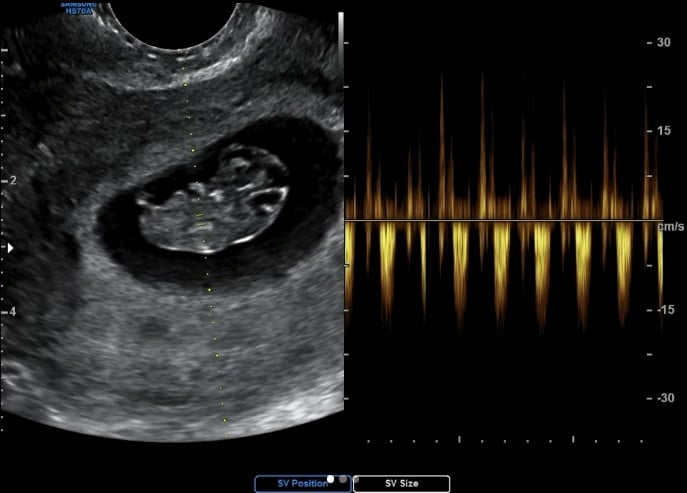

고우리는 지난 1일 자신의 인스타그램을 통해 "네 저 임신했어요❤️🎊🤰🏻"라며 한 장의 사진과 하나의 영상을 게재했다.

공개된 게시물들 속에는 고우리가 임신을 재차 확인하고 태아의 심장 소리를 녹화한 모습.